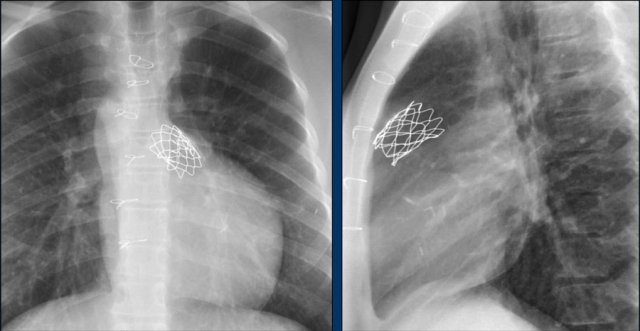

Here a patient with a larger defect, that was closed with two devices.